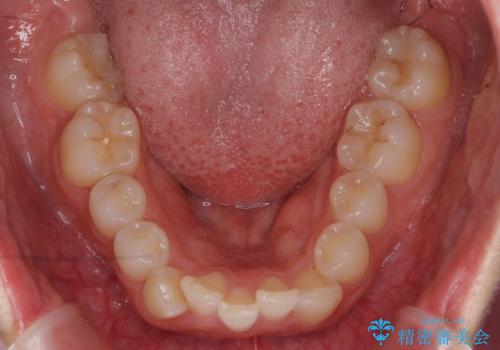

前歯をさげたい 歯を抜かずに マウスピース矯正で治したい

- 上の前歯が出ているとのことで来院。

歯を抜かずに、上の奥歯を後ろにさげつつ上の前歯を小さく少し削る処置を行い前歯の角度を修正しました。

右上下の奥歯もすれ違い咬合も、治療で改善しています。

下の前歯が生まれつき3本でしたので上下の正中は合わない仕上がりとなります。